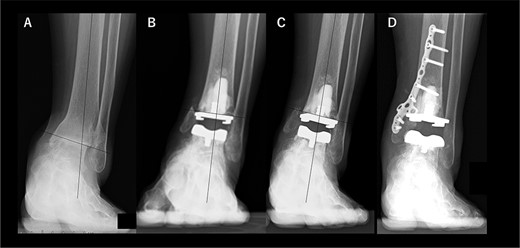

A 76-year-old woman with a 25-year history of RA [Clinical Disease Activity Index (DAS28-CRP score) 2.45: good control] had a JSSF ankle/hindfoot scale score of 42 points. She had been treated with 6 mg of methotrexate (MTX) per week. She complained of difficulty walking and ankle pain, resulting in an awkward gait. Talar tilt was 17° varus (Fig. 2A). She underwent TAA with medial malleolar osteotomy without internal fixation, and the tibial component was placed in the 2° varus position (Fig. 2B). Three years after TAA, she missed two or three steps while walking down the stairs. and developed anterior tibial pain. Radiography showed that varus migration of the tibial component had progressed (7° varus position; Fig. 2C), and she required revision TAA with internal fixation using a plate and allograft bone transplantation (Fig. 2D).

Radiographs of preoperative weight-bearing radiograph of the antero-posterior ankle joint in Case 2. (A) Preoperative. Talar tilt is 17° varus. Opening of the lateral gutter is seen. (B) One month after surgery. Medial malleolar osteotomy without internal fixation and the tibial component placed in the 2° varus position. Opening of the lateral gutter remains. (C) Three years after surgery. Varus migration of the tibial component has progressed after the patient missed the stairs (7° varus position of the component), and nonunion at the medial malleolar osteotomy has occurred. Opening of the lateral gutter has also remained. (D) Three months after revision surgery. Medial malleolar osteotomy site is fixed with a plate, and varus positioning of the tibial component still remains (3° varus). The lateral gutter is closed.